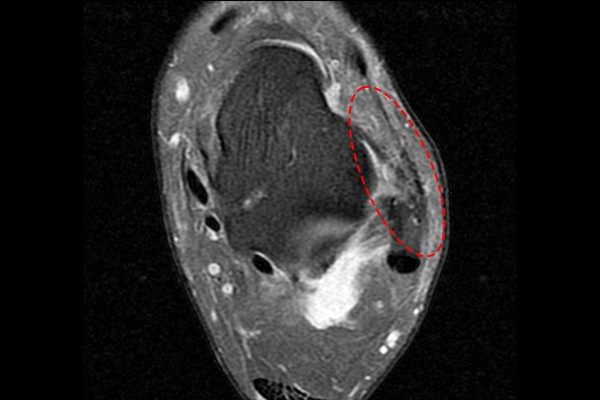

앞서 환자분께서 봉합술을 받았을 때, 계속 불편감을 느꼈다고 말씀하셨는데, 제 추측으로는 인대를 봉합할 때 안녹는 실을 사용하여, 시간이 지났음에도 발목에 계속 남아있어 불편감이 지속되지 않았을까 생각됩니다.(저는 발목인대를 봉합할 때 녹는실과 녹는 나사만을 사용합니다.)

수술실에서 전에 받으셨던 봉합술의 절개창을 보니, 안녹는 실이 확인되었습니다.

안녹는 실을 제거해주고,